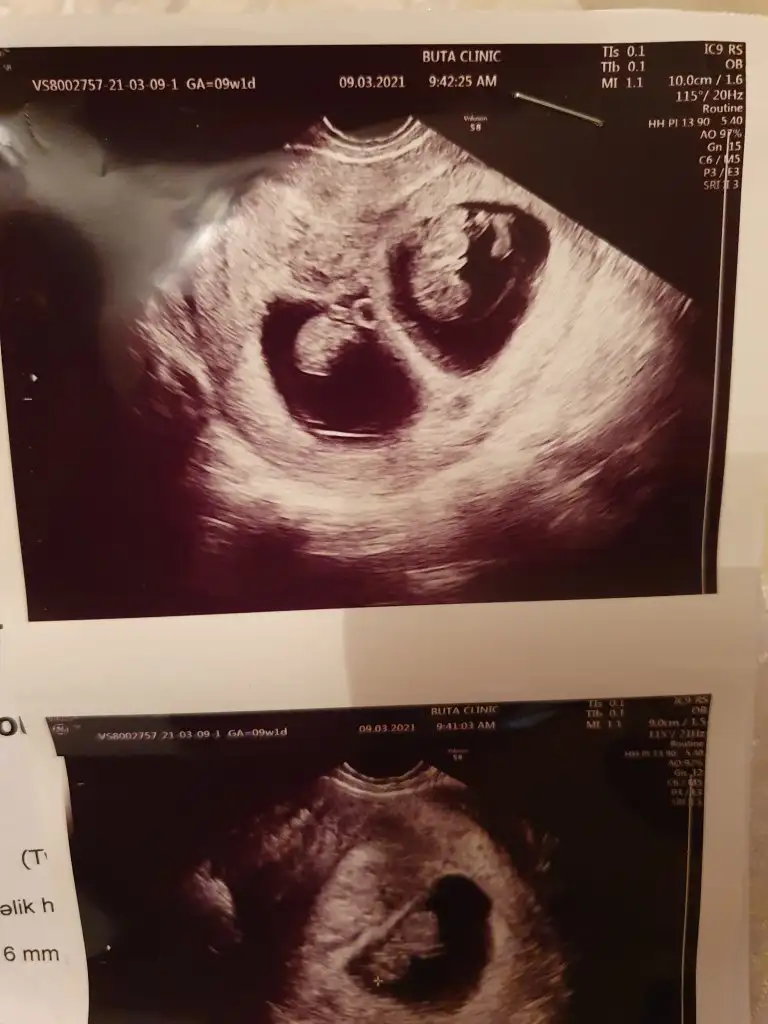

Merhaba şuan 10 haftalıgız çbuilk ultrasonumuz 5+5 iken cekildi. Ben basından beri kız hissediyorum Bi bakar mısın rica etsem? Dün sırf bunun için konu actım kimse yazmadı malesef. lütfen cevabını bekliyorum

Eklentiler

• Screenshot_20210318-175930.webp

18,3 KB · Görüntüleme: 190